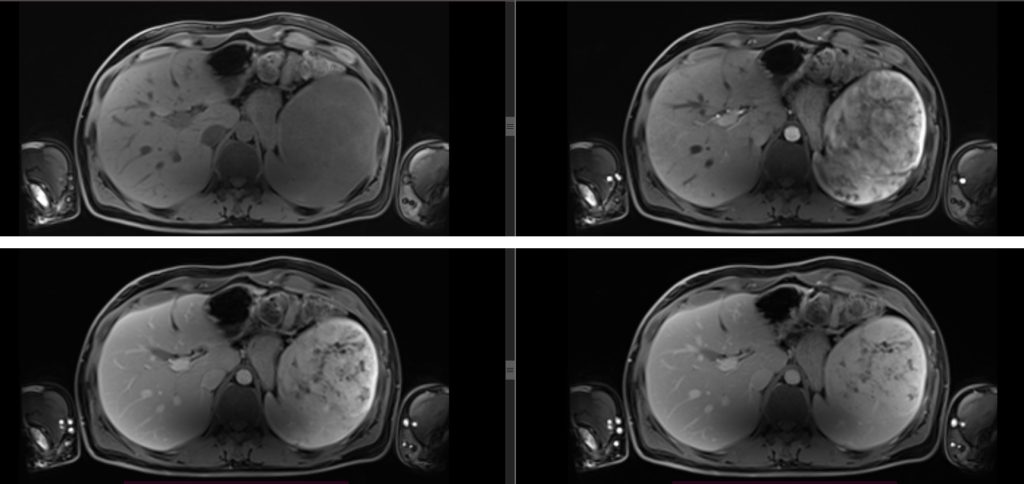

Figura 4: imagini în plan axial în ponderatie T1 pre si postcontrast dinamic